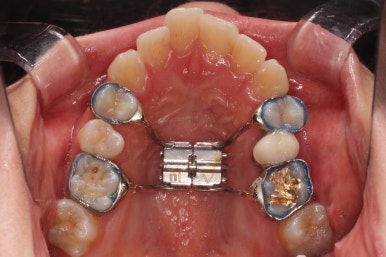

3. 치료경과

악궁확장을 먼저 시행합니다.

아랫니에 비해서 윗니의 악궁의 폭이 좁기 때문에 가로폭을 먼저 개선합니다.

Q. 미니스크류를 심고 악궁확장 해야 하나요?

저희 부산비대칭교정 키다리아저씨치과에서는 CT분석으로 악궁확장의 필요량, 필요 여부, 미니스크류를 이용해야 하는지 여부를 100%는 아니지만 높은 확률로 추정하여 시행합니다.

이번 환자분은 성인이긴 했지만 미니스크류 없는 일반 타입의 악궁확장장치로 시도하기로 했습니다.

악궁확장 이후, 유지단계 동안 확장의 유지에 필요한 치아를 제외하고는 브라켓을 부착하게 됩니다.